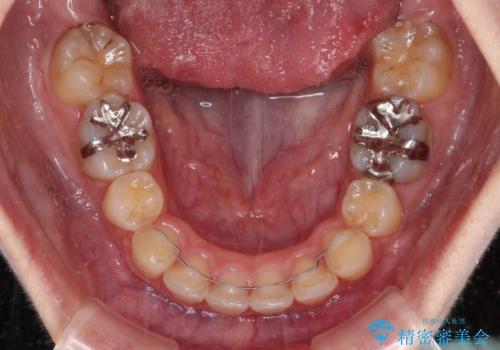

- 口元の突出感と口の閉じにくさを気にして来院された患者様です。

上下左右第一小臼歯4本を抜歯し、ワイヤー装置にて口元を引っ込めるよう矯正治療を行うこととしました。